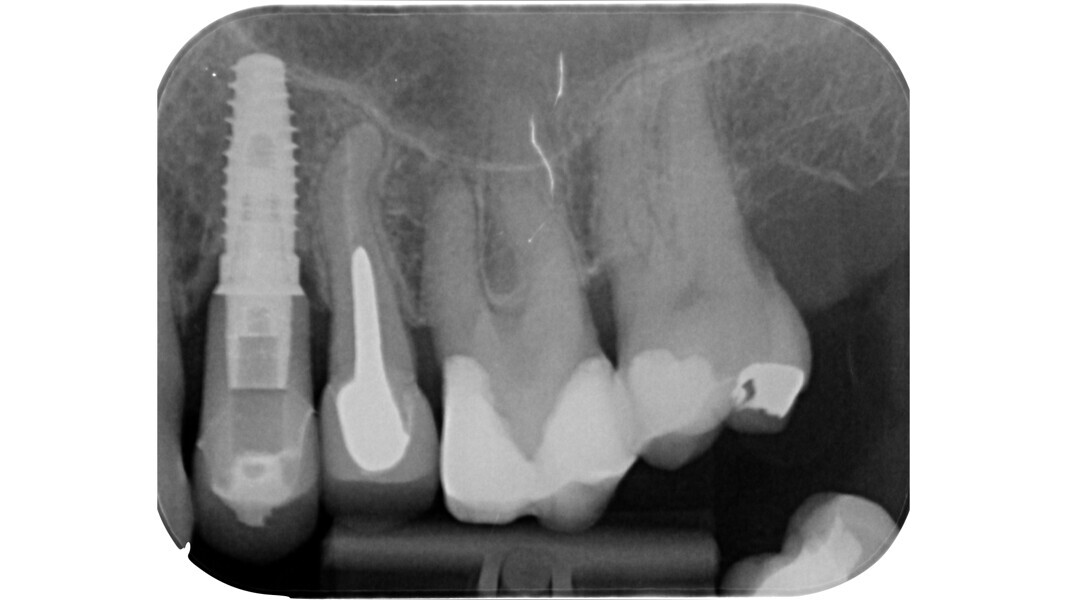

Fig. 6: Pre-op radiograph of a mesially tilted mandibular molar with irreversible pulpitis (probable colonisation from the distal periodontal lesion).

Fig. 7: Post-op radiograph showing the correct insertion axis during the preparation of the access cavity.

The current approach is towards a conservative access cavity that can guarantee enough visibility inside the pulp chamber to carry out shaping, irrigation and obturation, the pillars of endodontics. The first step to preparing an access cavity with these characteristics is the clinical and radiographic assessment of the tooth to be treated. The clinician should carefully evaluate the following important aspects that can yield valuable information for the approach to access cavity preparation: the position and inclination of the tooth (Figs. 6 & 7), the 3D extension of the carious process if present, the quality of pre-existing restorations and the relationship to the periodontium.